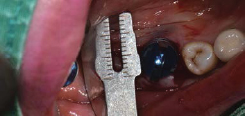

Point Drill 후 생성된 구멍에 Ø8.5 Volume Up Parallel Pin을 끼움

-

이 후, 앞의 임플란트 위치에 맞춰 Volume Up Gauge 위치 시켜 직경확인 (Ø7.5)

Volume Up Gauge 홈에 맞춰 Point Drill 위치